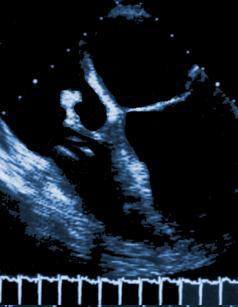

En el endocardio, generalmente en las válvulas, se forma una vegetación o verruga que es una masa donde anidan los microorganismos. Desde la vegetación los gérmenes invaden constantemente la sangre produciendo una bacteriemia persistente.

- Ecocardiograma: Demuestra la vegetación.

- Ecocardiograma positivos.